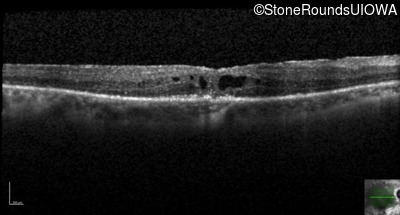

Age at visit: 66 years

OD OS

Age at visit: 65 years